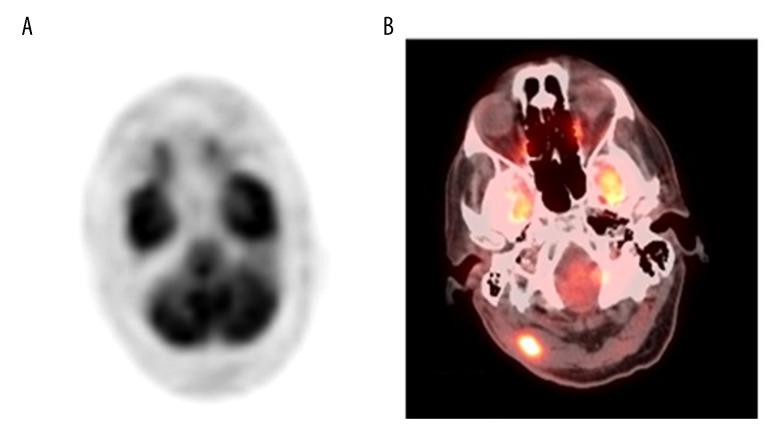

BACKGROUND Eccrine porocarcinoma, or malignant eccrine poroma, is a rare primary skin tumor that develops in the sixth and seventh decades of life, and can present as a painless and solitary nodule. Histopathology is required to confirm the diagnosis. A rare case is presented of metastatic eccrine porocarcinoma, occurring four years after surgical excision of the primary scalp tumor, and includes a review of the literature. CASE REPORT A 67-year-old man initially presented with a scalp lesion that was non-painful, exophytic, and pigmented. Following complete excision, histopathology confirmed the diagnosis of eccrine porocarcinoma with clear resection margins. Four years later, he presented with discrete erythematous patches and plaques, in a zosteriform distribution, in the skin of the right neck, shoulder, and chest. A biopsy and histopathology of the skin rash confirmed metastatic eccrine porocarcinoma. A positron-emission tomography-computed tomography (PET-CT) scan identified areas of hypermetabolic activity, with a standardized uptake value (SUV) of 12, and an infiltrating soft tissue tumor in the right suboccipital region. Surgical resection of the suboccipital mass, followed by histopathology, confirmed metastatic eccrine porocarcinoma. During a postoperative ear, nose, and throat (ENT) examination, he was found to have metastases in the right ear canal. The patient received five cycles of chemotherapy, but later developed renal failure and eventually chose palliative care. CONCLUSIONS A rash-like presentation of skin metastasis to the trunk and metastasis to the ear from a primary eccrine porocarcinoma is rare. Early diagnosis and adequate surgical resection are recommended to reduce patient mortality.

背景 小汗腺汗孔癌,或恶性小汗腺汗孔瘤,是一种罕见的原发性皮肤肿瘤,好发于60至70岁,可表现为无痛性孤立结节。确诊需依靠组织病理学检查。本文报告一例罕见的转移性小汗腺汗孔癌病例,该病例发生于原发性头皮肿瘤手术切除四年后,并对相关文献进行了回顾。病例报告 一名67岁男性最初表现为头皮出现无痛性、外生性、色素沉着的病变。完整切除后经组织病理学检查确诊为小汗腺汗孔癌,切缘清晰。四年后,他在右颈部、肩部和胸部皮肤出现呈带状疱疹样分布的散在红斑和斑块。对皮疹进行活检及组织病理学检查确诊为转移性小汗腺汗孔癌。正电子发射断层扫描-计算机断层扫描(PET-CT)显示高代谢活性区域,标准化摄取值(SUV)为‘12’,右枕下区域有一个浸润性软组织肿瘤。对枕下肿块进行手术切除,术后组织病理学检查确诊为转移性小汗腺汗孔癌。术后耳鼻喉检查发现其右耳道有转移灶。该患者接受了五个周期的化疗,但后来出现肾衰竭,最终选择姑息治疗。结论 原发性小汗腺汗孔癌出现皮疹样皮肤转移至躯干及转移至耳部的情况较为罕见。建议早期诊断并进行充分的手术切除以降低患者死亡率。 (注:原文中SUV值‘12’表述有误,一般SUV值会保留一位小数,这里按照正确翻译思路给出译文,实际临床中应按正确数值为准)